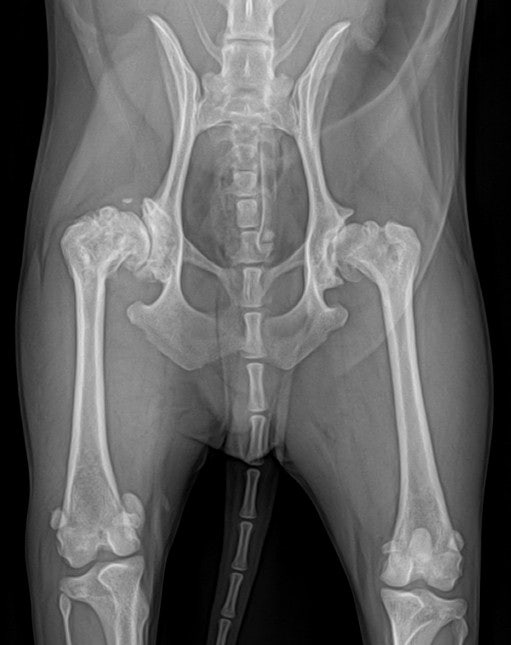

관절성형술은 퇴행성관절염의 대표적인 외과적 치료법으로 연골 손상, 관절 변형이 심해 무릎 관절이 정상적으로 기능하지 못하는 경우 손상된 관절을 제거하고 인공관절을 삽입해 관절 운동 기능을 회복하고 기저 통증을 치료한다. 환자의 상태에 따라 전치환술과 부분치환술로 나뉩니다.관절 교체

무릎 인공관절 수술은 손상된 부분만 대체하는 부분관절치환술과 무릎관절 전체를 대체하는 전치환술로 나뉜다. 환자마다 관절의 크기와 손상 정도가 다르기 때문에 전문의와의 상담을 통해 개인차를 파악하고 적절한 치료를 받는 것이 중요합니다.

인공관절 전치환술 부분치환술 최소절개 10~12cm 최소절개 5~7cm 무릎관절이 광범위하게 손상되었을 때 “전체” 관절을 교체 손상된 무릎관절의 “일부”를 인공관절로 교체 효과적인 O자형 다리교정 출혈이 적고, 비교적 빠른 회복